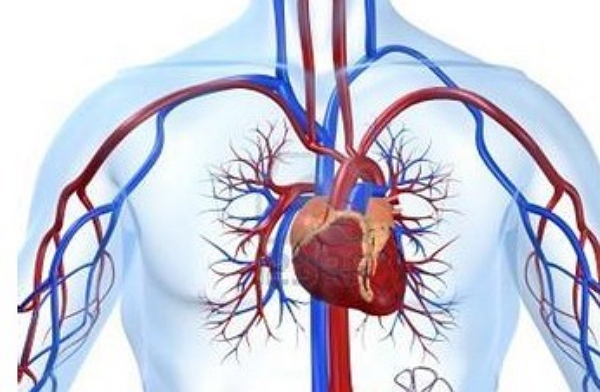

往左側睡眠還能幫助心臟省力,改善心血管循環的健康,

因為側向左邊睡時大動脈的流向是往下更能有效幫助心臟向下輸送血液,

而血液流回心臟也會變的更有效率。